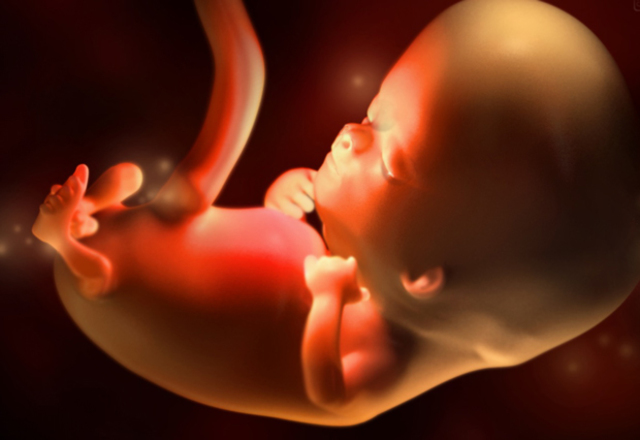

SEMANA 30

Su cerebro ha crecido y se acomoda al tamaño de su cabeza, sus pulmones continúan madurando, comienza a buscar la posición definitiva que tendrá al nacer.

SEMANA 29

Mide 35 centimetros y pesa alrededor de 1.100 gramos, comienza a redondearse, ya no parece tan flaco.